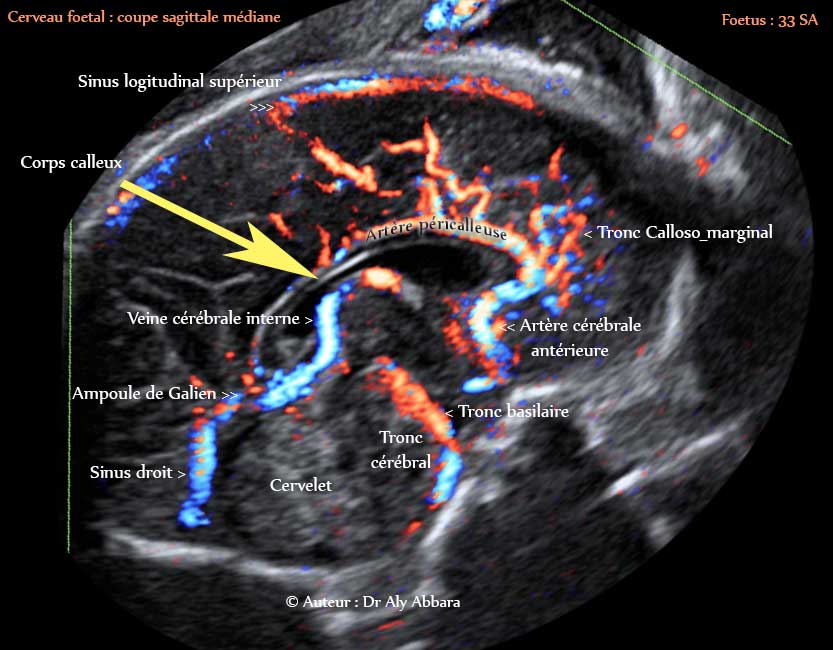

Coupe sagittale médiane du cerveau foetale - vaisseaux sanguins et les structures anatomiques identifiable à 33 SA - échocardiographie

Image échographique animée montrant les vaisseaux sanguins et les structures anatomiques identifiables sur une coupe sagittale médiane stricte du cerveau foetal à 33 SA.